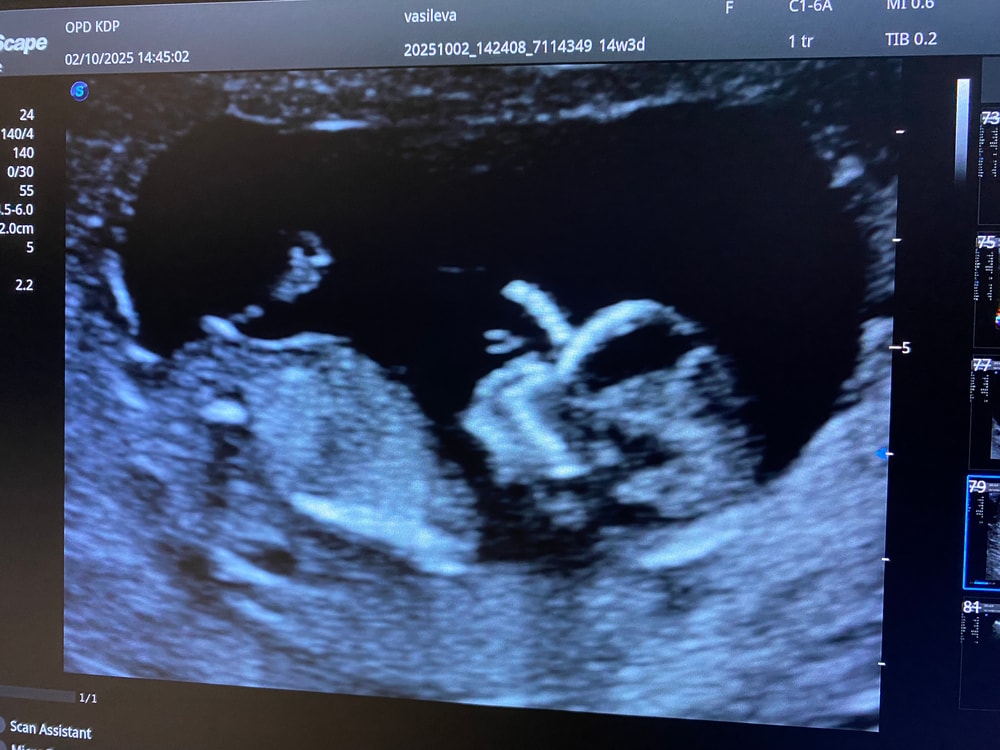

на первом узи в 12 недель врач сказал у вас девочка (но конечно верить не могу на первом узи, так как в 12году с сыном до 3 скрининга говорила девочка, а со вторым в принципе все время говорили мальчик, один раз не поняли кто 😅)

на втором узи в 20 недель врач дал конверт в котором было написан